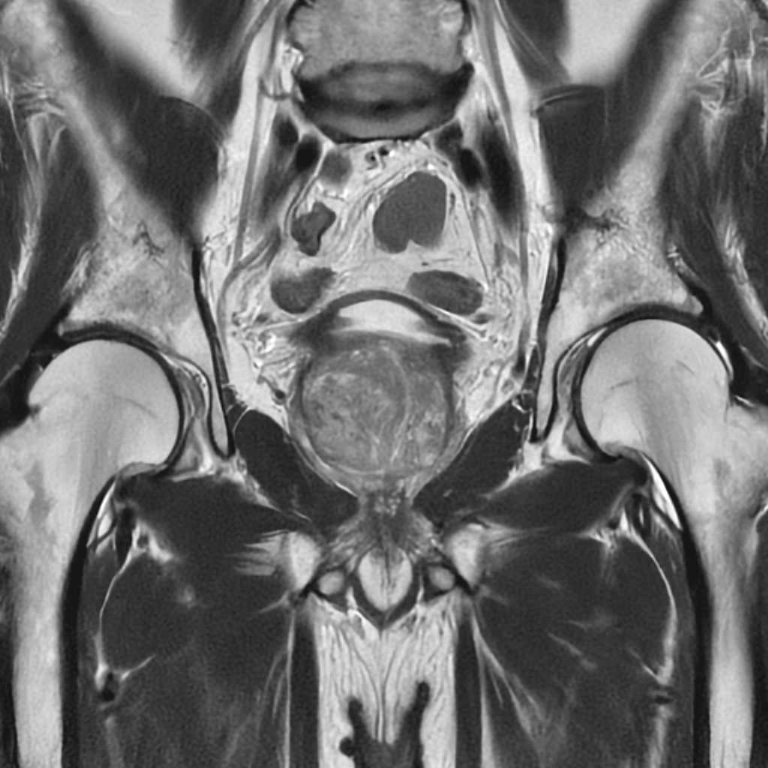

MRI検査

男性器領域

前立腺

前立腺肥大